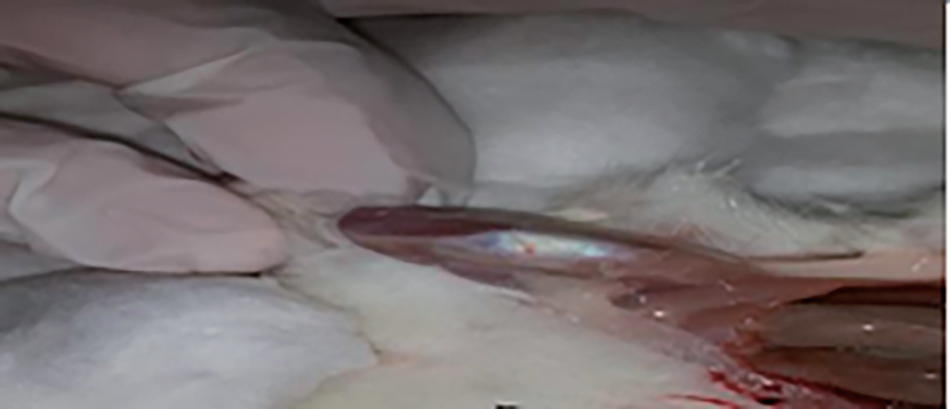

Results on OA rats showed the articular cartilage surface degradation, dense fibrous tissue, destruction and punctuate depression, erosion, glossy surface, and bone destruction of OA knee joints compared with OA treated with vitamin D3 and control rats which appeared with normal cartilage surface, smooth and intact, in addition, the pictures revealed to normal patella and normal tendon on articular cartilage region of treated rats with vitamin D3 compared to control pictures, (Figs. 5–7).

Fig. 7. Image on knee joint from treated rats with vitamin (D3) showed normal patella () and normal tendons ().